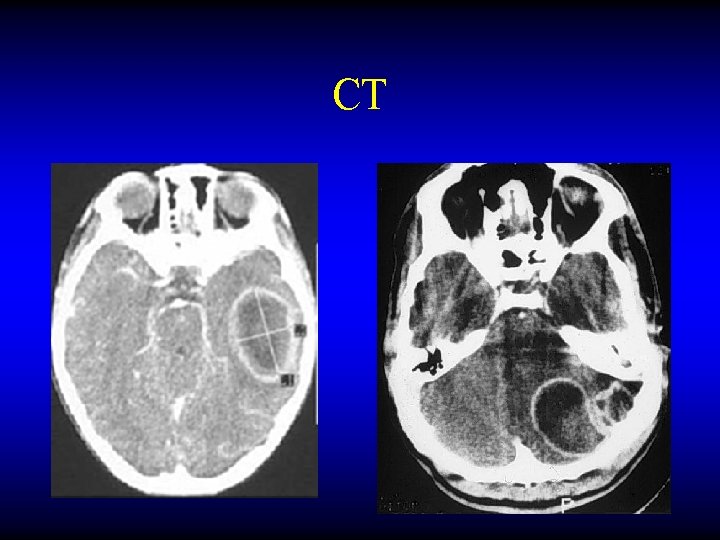

Otogenic brain abscess Diagnosis • CT • MRI

CT

MRI